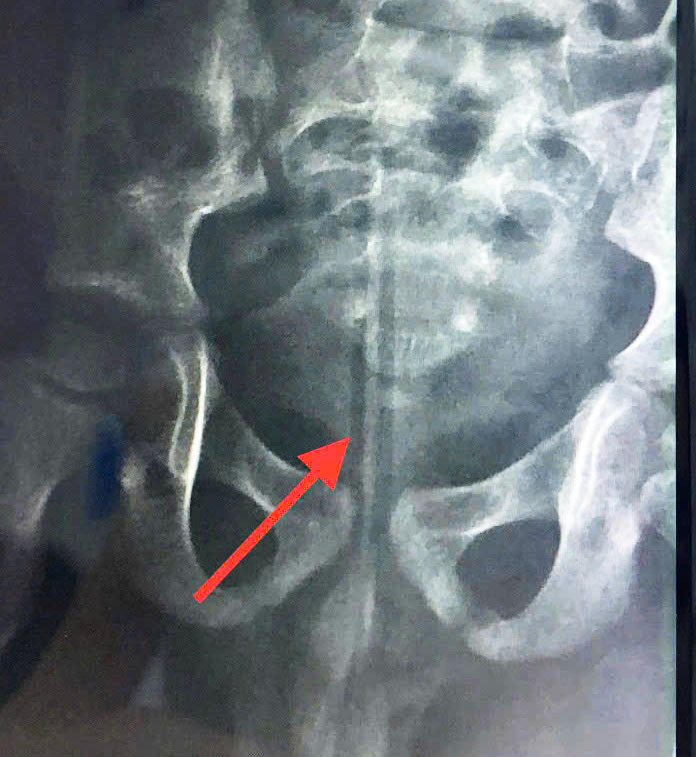

Sự việc xảy ra vào buổi trưa khi mẹ bé đang làm việc nhà và nghe con than đau. Sau khi bé tự khai nhận, gia đình lập tức đưa trẻ đến cơ sở y tế gần nhà, chụp X-quang ghi nhận dị vật trong khung chậu và được hướng dẫn chuyển đến Bệnh viện thành phố Thủ Đức.

| Hình ảnh chụp chiếu ghi nhận dị vật trong vùng kín bé trai. Ảnh BVCC |